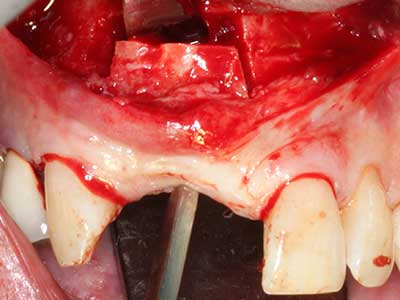

Пиезохирургията има допълнителни предимства при събиране на костни блокове. В допълнение към високата прецизност при остеотомията, описана по-горе, употребата на фините режещи накрайници значително намаляват загубата на материал. Голяма загуба на материал по време на събиране може да се очаква с дебелите накрайници, особено при употреба на борери Линдеман (Lakshmiganthan, Gokulanathan et al. 2012). Базалното разделяне, което е необходимо, особено за присадка на блок при ретромолар, е улеснено от специално създадени правоъгълни триони. В резултат на това, пиезохирургията е разглеждана като прецизна, улеснена и безопасна процедура за събиране на костни блокове в ретромоларното пространство (Happe 2007) (Фиг. 1-12).